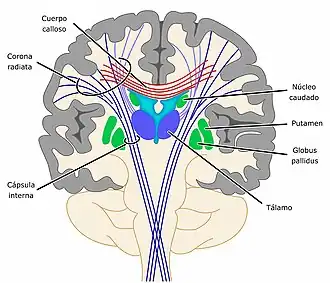

En la superficie del cerebro de los vertebrados se encuentra la corteza cerebral que está formada por sustancia gris, por debajo se sitúa una masa central de sustancia blanca que envuelve un conjunto de núcleos de sustancia gris situados en el centro del cerebro, entre los que se incluye el tálamo y los llamados ganglios basales o núcleos basales.[12]

Ganglios basales

Los ganglios basales en realidad deberían llamarse núcleos basales pues no son verdaderos ganglios. Son un conjunto de estructuras cerebrales formadas por sustancia gris que están situados debajo de la corteza y desempeñan importantes funciones, una de las principales es el control de los movimientos voluntarios, pero también intervienen en el procesamiento de la información sensorial y en aspectos relacionados con la memoria y las emociones. Están conectados con la corteza cerebral y funcionan con un alto grado de integración. Pueden diferenciarse los siguientes:[29]

- Cuerpo estriado, formado por el núcleo caudado, el putamen y el núcleo accumbens.

- Globo pálido.

Cuerpo calloso

Cápsula interna

La cápsula interna es un grueso conjunto de fibras nerviosas tanto ascendentes como descendentes que comunican la corteza con las regiones inferiores del sistema nervioso central, las fibras son de origen diverso, pero muchas de ellas transportan información motora o sensitiva. En su trayecto pasan cerca de la región del tálamo y los ganglios basales. La cápsula interna es una región muy sensible, cualquier lesión en esta zona daña numerosas fibras nerviosas y provoca en consecuencia déficits neurológicos graves.[28]